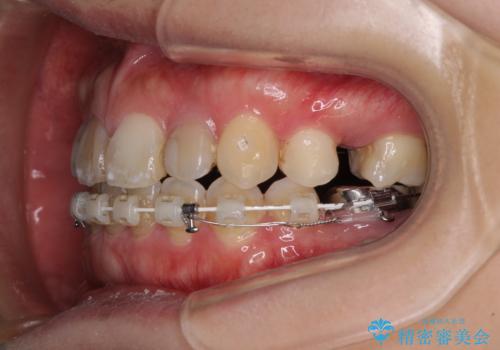

- ハーフリンガル

抜歯矯正が必要であることはご自身で理解されており、目立たない装置をご希望であったので、上顎が裏側装置であるハーフリンガル装置にて治療を行うこととしました。

開咬の改善には舌突出癖を改善するためのトレーニングが必要ですが、しっかりと行っていただき、想定よりも早い期間で治療を終えることができました。